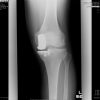

An 80-year-old Chinese lady with symptomatic left medial knee osteoarthritis confirmed on weight-bearing knee radiographs (Fig. 1) presented to our outpatient clinic. Having failed a period of conservative treatment, she subsequently underwent a left medial OUKA successfully. A cementless size XS femoral implant and a cementless size AA tibial implant with a 5 mm mobile bearing insert were used. Post-operative recovery was uneventful, and radiographs done showed satisfactory prosthesis positioning with no evidence of periprosthetic fractures (Fig. 2). The patient managed to ambulate well on the 1st post-operative day and was transferred to a step-down facility for further rehabilitation.